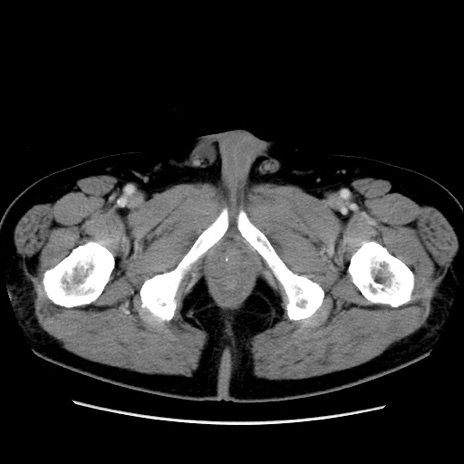

症例16(横断像)

【症例】 70歳代男性

【主訴】 腹痛、嘔吐

【現病歴】 約1ヶ月前より間欠的に腹痛と嘔吐あり、当院消化器内科を受診したところCTで多発する肝臓のLDAを指摘され、精査中であった。以降は消化器症状は安定していたが、2日前より嘔気と腹痛があり、同日より排便・排ガスが消失した。改善認めず、 本日、救急外来を受診した。

【既往歴】 大腸ポリープ切除後。

【身体所見】意識清明・会話良好、BT 36.3℃、BP 127/80mmHg、 P 80bpm、腹部:膨満あり、平坦・軟、上腹部正中および下腹部正中に圧痛あり、反跳痛なし、筋性防御なし。

【データ】WBC 7200、CRP 0.77